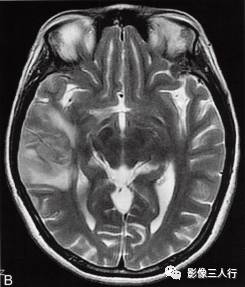

图1右颞叶横纹肌样脑膜瘤

A.T1WI横断面;B、C.T2WI横断面;D、E、F、G.增强横断面、矢状面、冠状面;H.HE×100

图1A:MRI T1WI示,右侧颞叶不规则形肿块,信号欠均匀,为稍低信号与小斑片状稍高信号混杂。其累及颞叶灰白质,界限欠清、边缘不整,大小约4.1cm×4.3cm×5.1cm。邻近脑沟脑裂变浅变平,周边脑实质受压。图1B、C:T2WI示,右颞不规则形肿块,信号欠均匀,为稍高信号与小斑片状略低信号混杂。灶周见带状高信号脑水肿。图1D~G:T1WI C示,右侧颞叶肿块呈不均匀的多个结节块状明显强化,邻近脑膜为线条状强化、增厚。